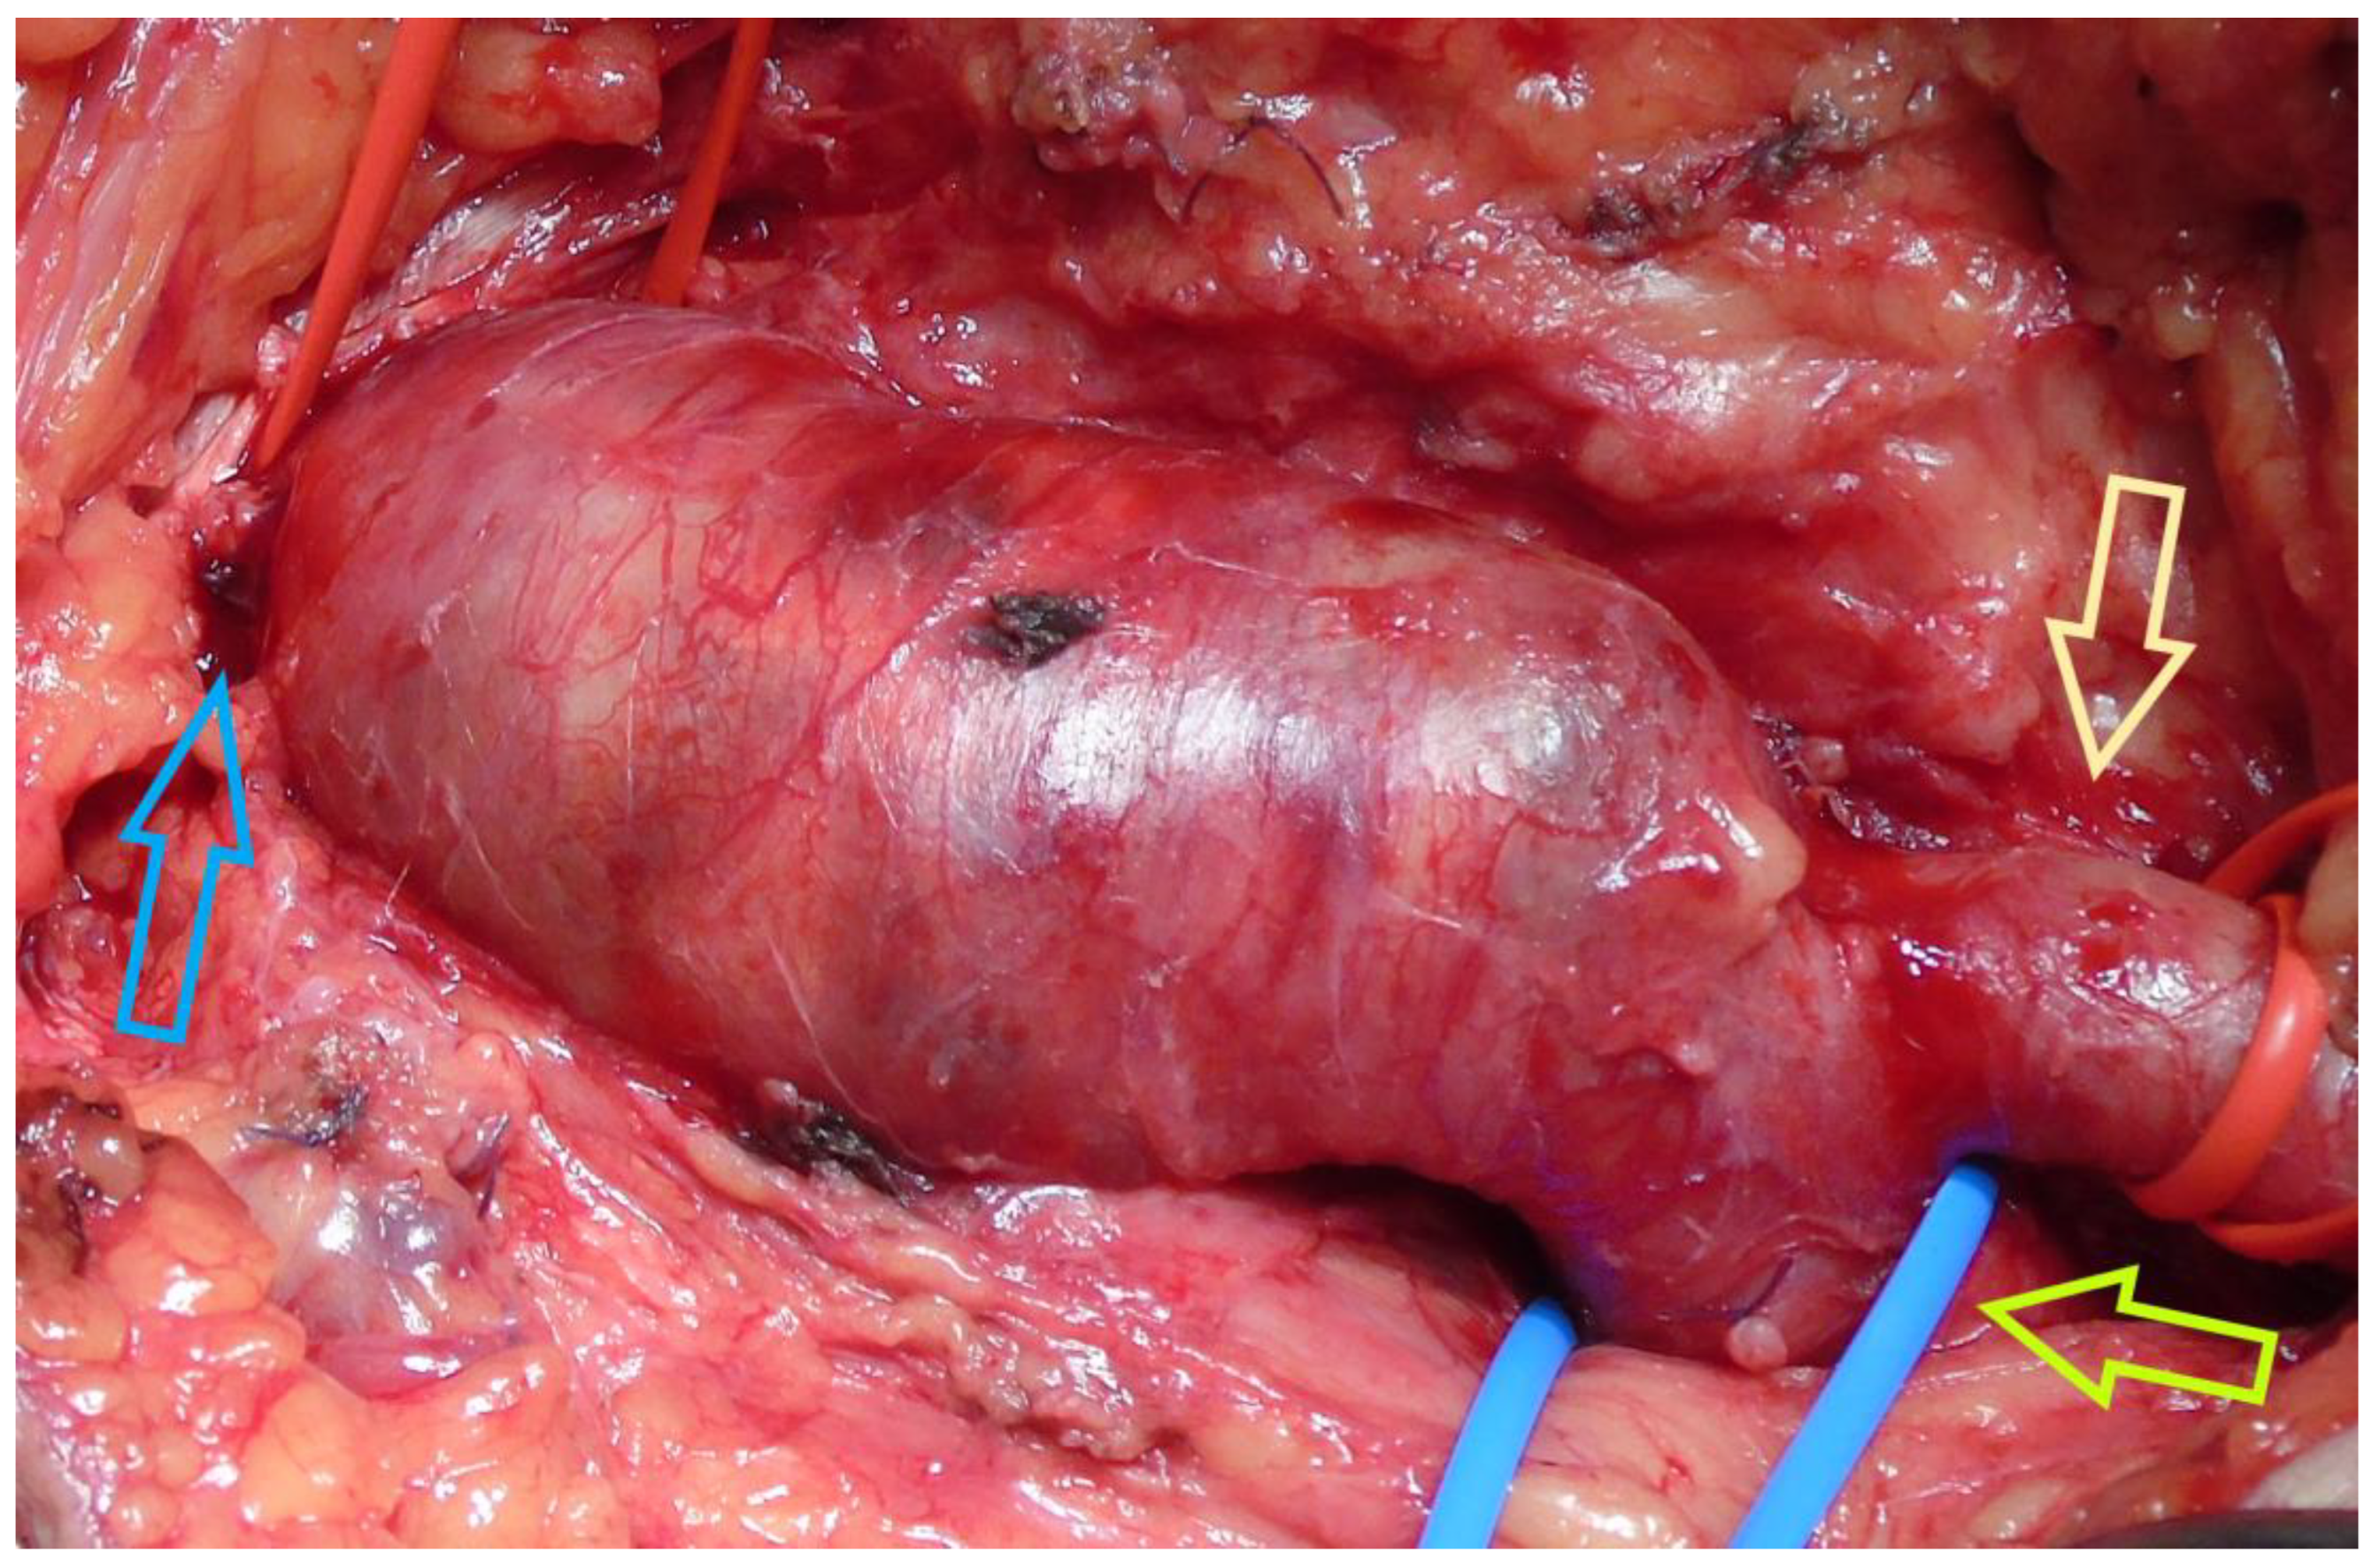

3.1. Case 1

3.2. Case 2

3.3. Case 3